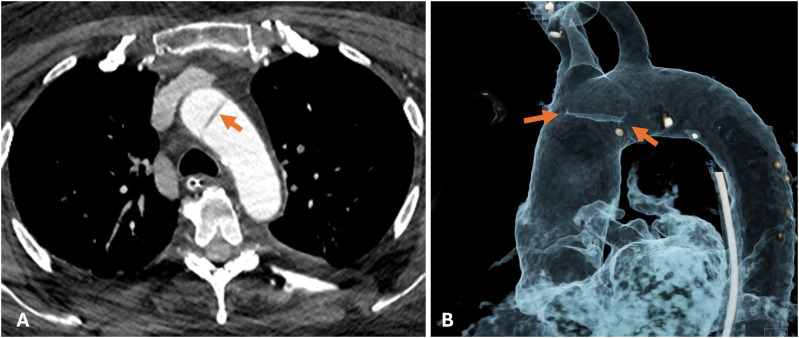

背景:随着越来越多地使用成像技术诊断人体病理,越来越多新的主动脉异常被发现。主动脉内索就是这样一种异常,需要与夹层的内膜瓣区分开来,以避免大手术或长期监护。本研究的目的是利用容积渲染重新格式化技术,提出主动脉内索在成像上的独特特征,并确定已发表文献中的类似发现,从而确定 "小酒窝 "征的作用:方法:回顾本院的成像(2 例)和已发表的文献(6 例),以确定主动脉容积渲染成像中是否存在诊断征象:结果:"酒窝征 "是主动脉内索特有的征象,在之前发表的 6 篇文献中,有 4 篇的图像中出现了这一征象。有两篇文章没有使用容积渲染。包括我们的病例在内,8 个病例中有 6 个出现了 "酒窝征"。出现 "酒窝 "征的原因是脐带拴系在主动脉壁上,导致主动脉壁向内脐化发展:结论:"酒窝 "征在容积和/或电影渲染中很容易观察到,是诊断主动脉内脐带的有用征象,有助于将其与内膜瓣区分开来。

BackgroundWith increasing use of imaging to diagnose human pathology, newer aortic anomalies are being identified. An intra-aortic cord is one such abnormality, which requires differentiating from an intimal flap of dissection, to avoid major surgery or prolonged surveillance. The aim of this study was to bring forth a unique feature of the intra-aortic cord on imaging, using volume rendering reformatting and identify similar findings in published literature and hence establish the role of the 'Dimple' sign.MethodsReview of both our institutional imaging (2 cases) as well as the published literature (6 cases), to identify presence of a diagnostic sign that is seen on volume rendered imaging of aorta.ResultsThe 'Dimple sign' is unique to the intra-aortic cord and is noted on the images of 4 out of 6 prior publications. Two publications did not use volume rendering. Including our cases, the Dimple' sign is seen in 6 out of 8 cases. The Dimple sign arises due to tethering of the cord to the aortic wall leading to umbilication of the aortic wall inwards.ConclusionsThe Dimple sign can be very easily noted on volume and/or cinematic rendering and is a useful sign to diagnose an intra-aortic cord and help differentiate it from an intimal flap.